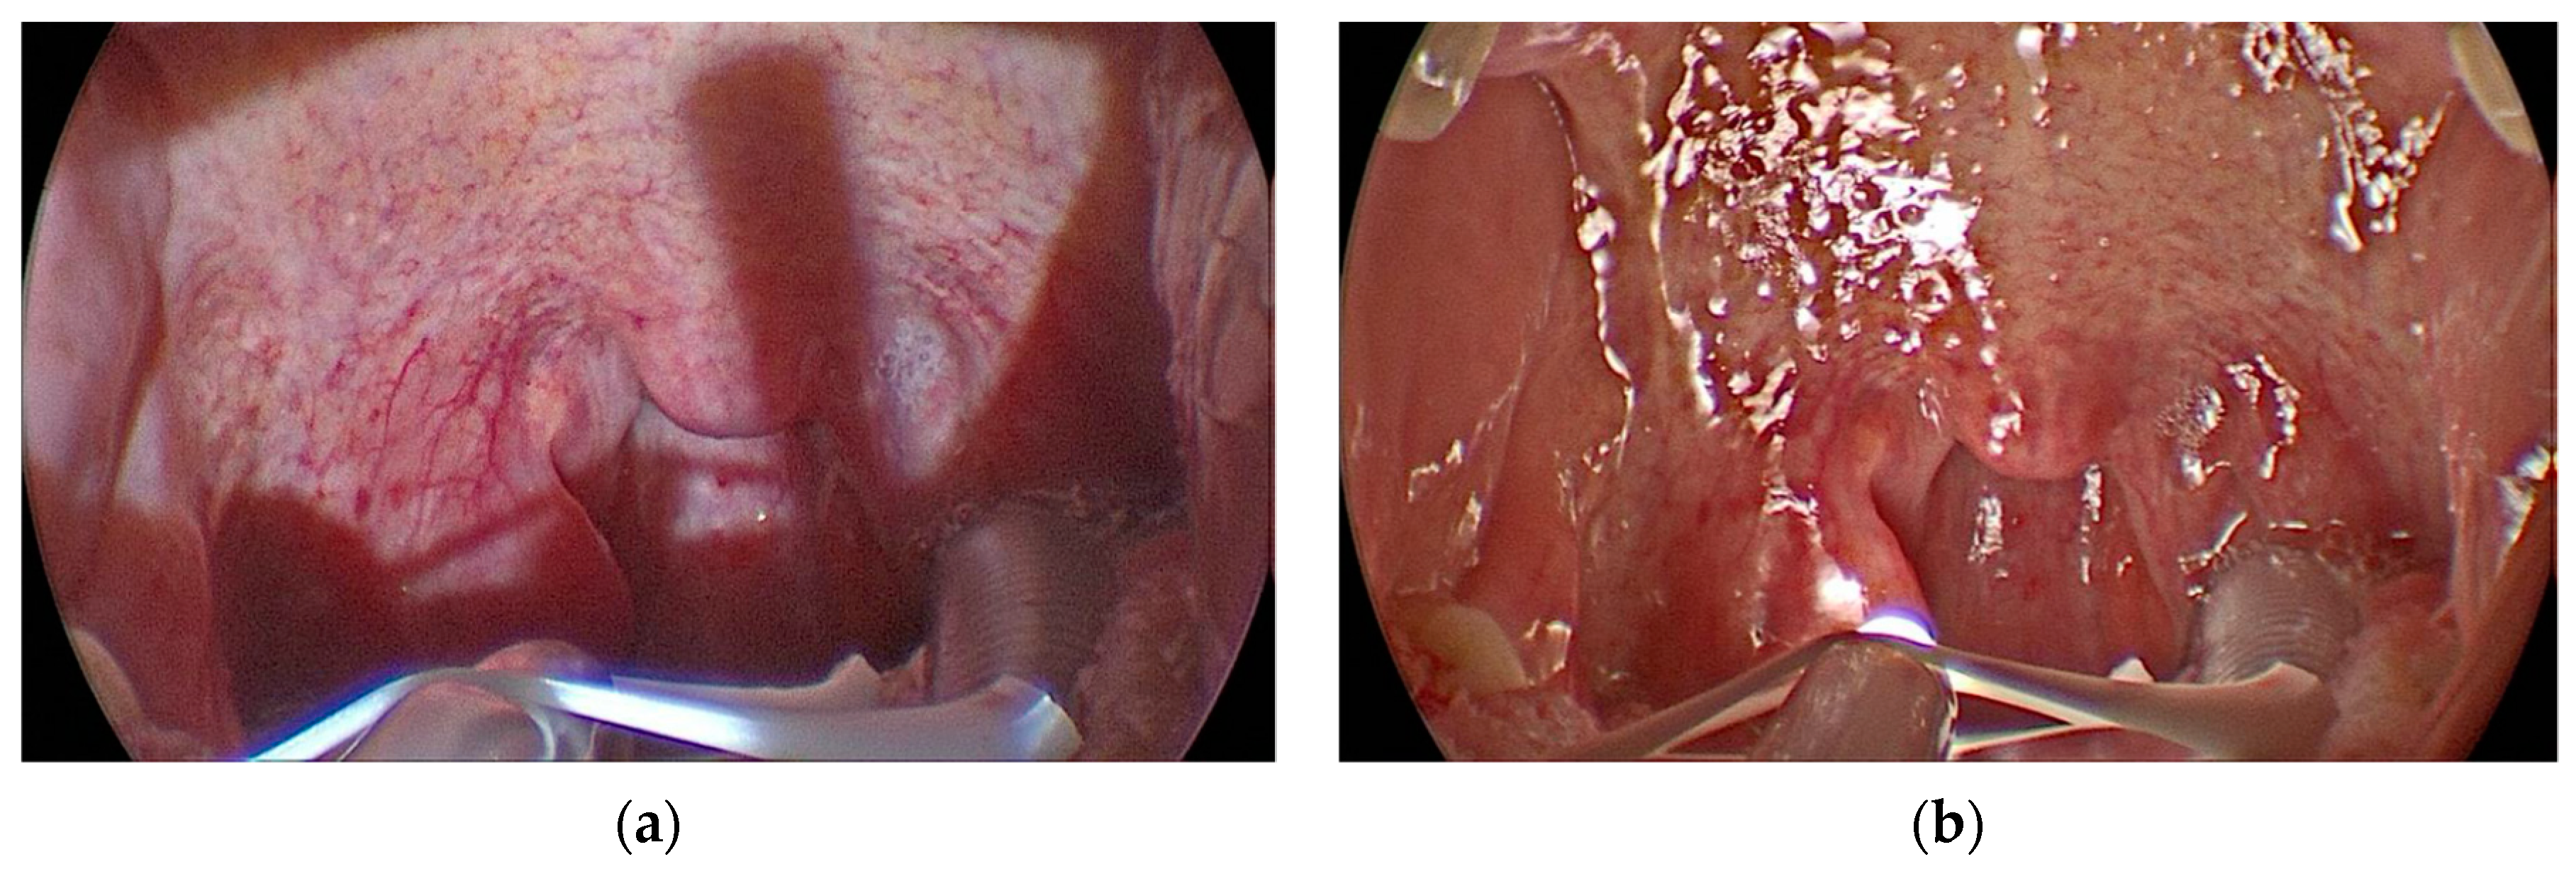

On each patient, the procedure was performed by an expert surgeon: on one half of the palate with the headlamp and the other half with KlaroTM illumination system; the residents attended the surgical procedures, which were filmed with a 70° rigid endoscope and transmitted on the screen (Figure 3A,B).

The quality of visualization on the screen was statistically significantly better with KlaroTM versus Headlamp to identify the fibres of the palatopharyngeal muscle and to recognize the entrance and exit point of the sutures and the needle tip (Table 2). The uniformity of vision and the absence of shadows on the screen during the use of KlaroTM made the image more uniform and enjoyable (Fig 3 A,B). Also, the residents did not report significant differences for the visualization of posterior pharyngeal wall and uvula.

Figure 3. (a) Oropharynx lighting with headlamp; (b) Oropharynx lighting with KLAROTM.